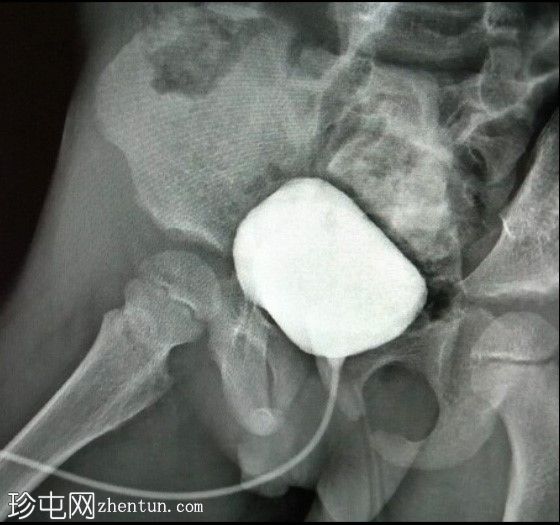

斜位

侧位影像显示膀胱后方可见一管状结构,可能为阴道,且充满造影剂。这提示膀胱与阴道之间存在共同的会阴开口。然而,这些影像并未显示该结构之间的瘘管连接。